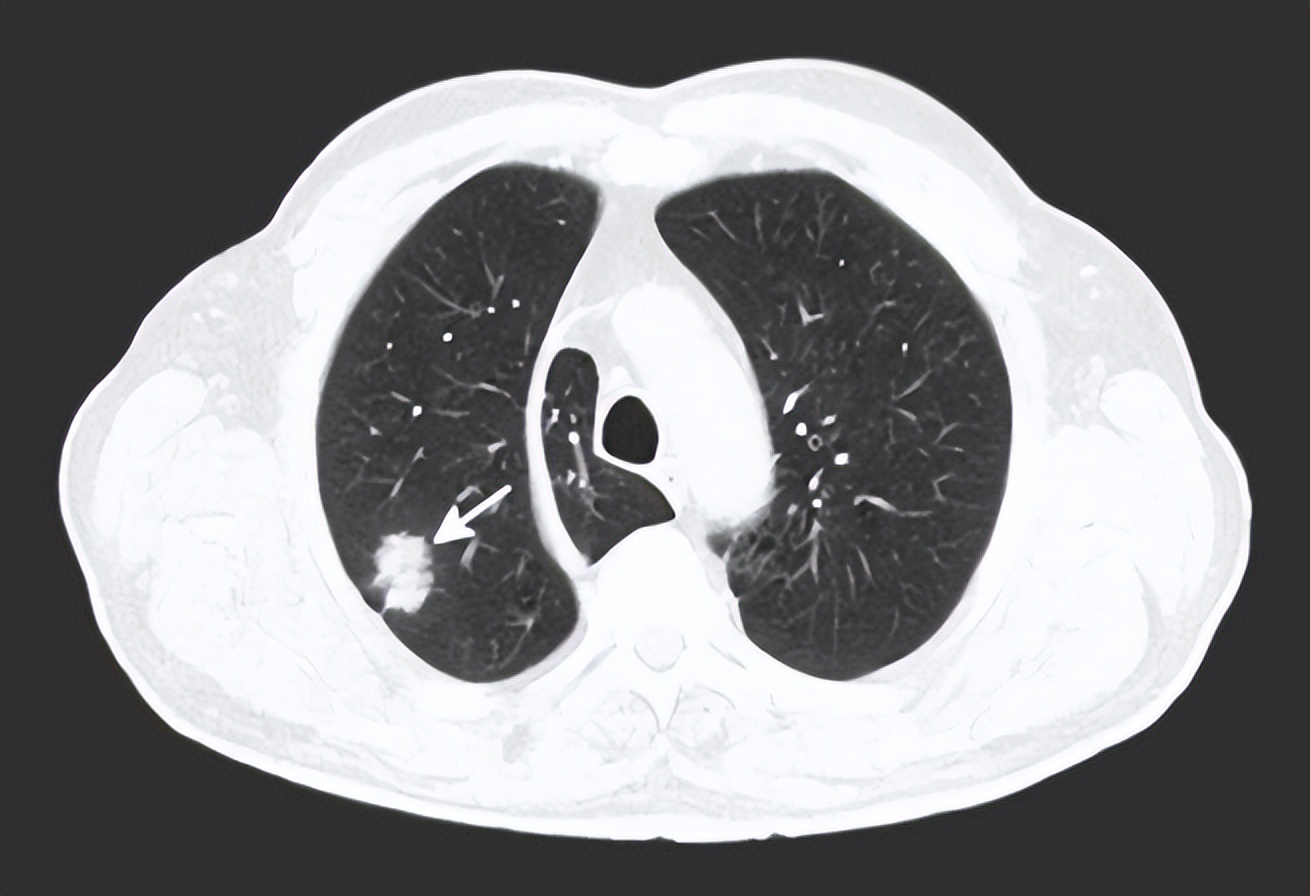

福建漳州就有一名男子因经常闻臭袜子导致肺部感染住院:

该男子最开始只是咳嗽,后来逐渐加重,还伴随着胸闷的问题,经过医院进一步诊断,发现他是肺部真菌感染——即真菌引起的 支气管肺部真菌感染 。